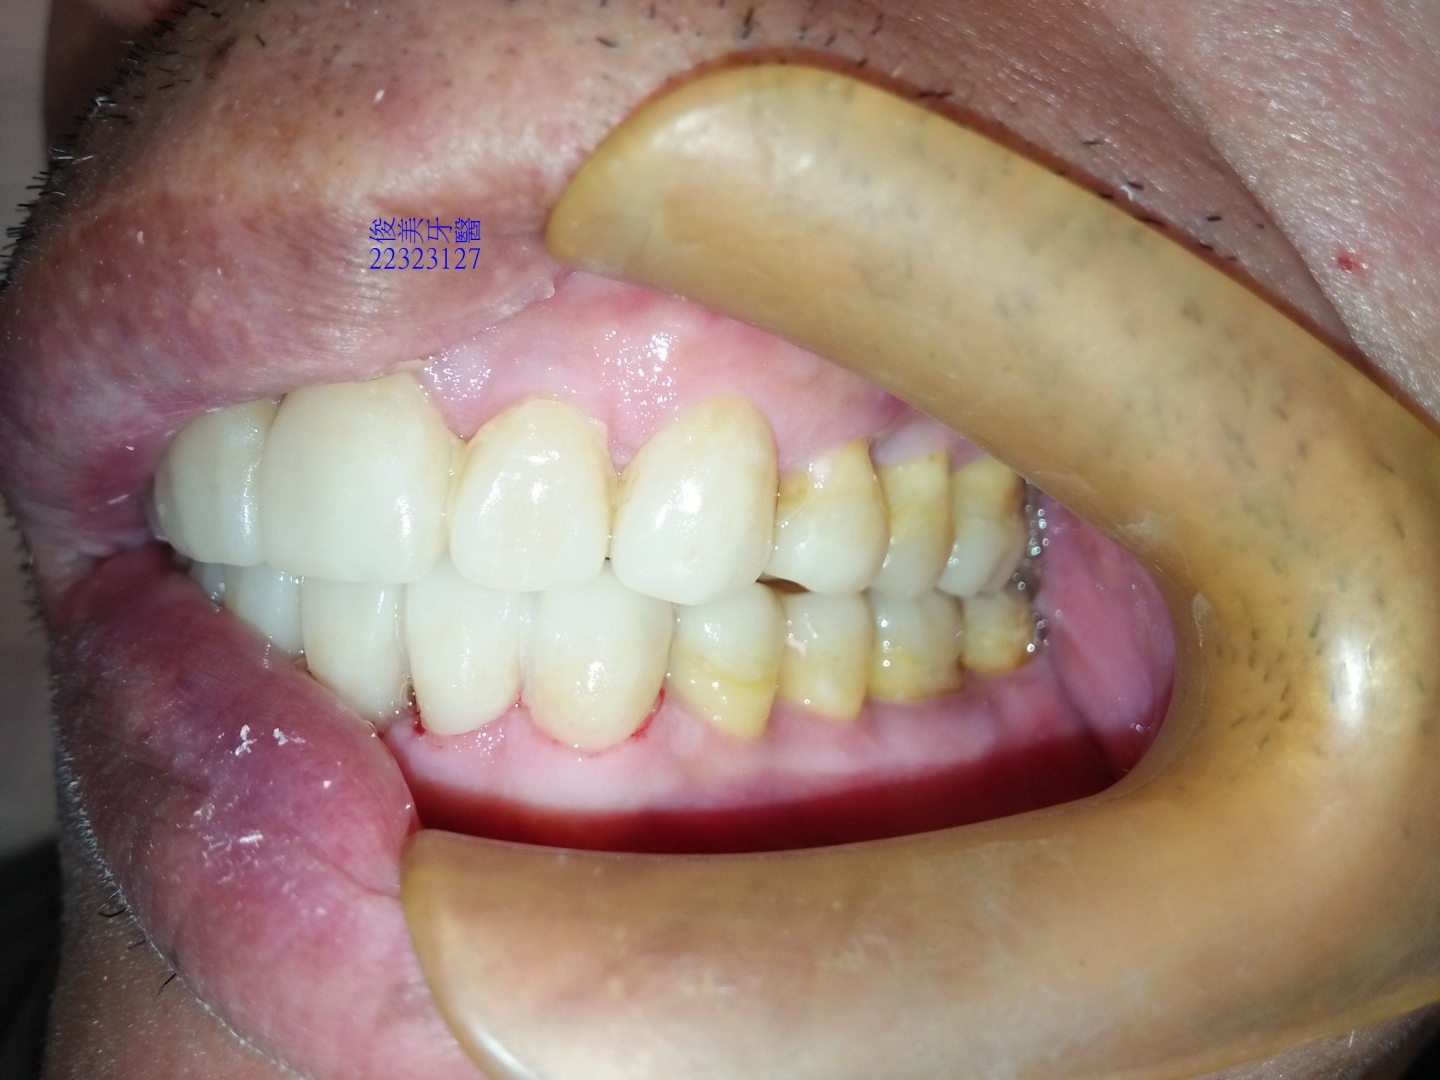

後牙高度已建立,恢復琺瑯質的厚度。